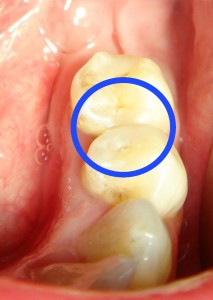

Поверхностный кариес. Дефект эмали, визуально обнаруживаемый на доступных обозрению поверхностях зуба. При остром течении дефект обычно имеет округлую или овальную форму, неровные, как бы зазубренные края, по цвету мало отличается от непораженной эмали. Дно и стенки такого дефекта достаточно плотны. При зондировании обнаруживается их шероховатость. Края дефекта безболезненны, а прикосновение инструмента к его дну может быть чувствительным. При воздействии холодом может возникнуть болевая реакция. В эмали зуба, примыкающей к такому дефекту, какие-либо изменения обычно не отмечаются. При хроническом течении поверхностный кариес проявляется также в виде дефекта эмали, практически не вызывающего неприятных субъективных ощущений. Лишь при локализации дефекта на апроксимальной поверхности зуба могут появляться жалобы на застревание пищи. На доступных глазу поверхностях дефект эмали хорошо виден: его стенки и дно коричневого цвета либо желто-коричневого, плотные при зондировании, как правило, безболезненные. Обычно дефект имеет четкие сферические очертания.